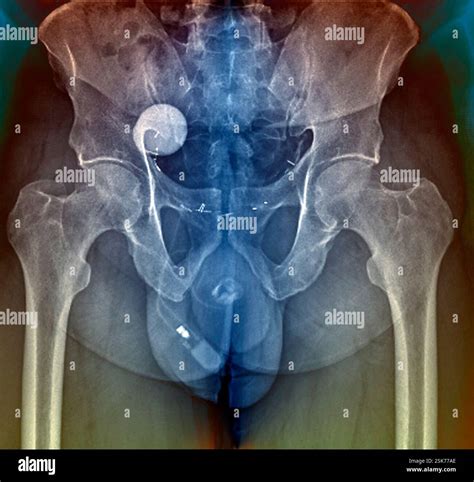

An Artificial Urethral Sphincter is a surgically implanted device designed to mimic the function of the natural sphincter muscle, which normally keeps the urethra closed to prevent urine leakage. When this natural muscle is damaged or weak, the AUS takes over the responsibility of controlling the flow of urine. The device is entirely contained within the body, making it discreet and effective for long-term use.

The system typically consists of three interconnected components:

• The Cuff: A circular balloon placed around the urethra that inflates to keep the urethra closed.

• The Pump: A small control mechanism placed in the scrotum (for men) or labia (for women) that allows the patient to manually deflate the cuff when they need to urinate.

• The Balloon (Pressure-Regulating Reservoir): A reservoir implanted in the abdomen that regulates the pressure within the system to ensure the cuff stays closed yet comfortable.

• artificial urethral sphincter radiology